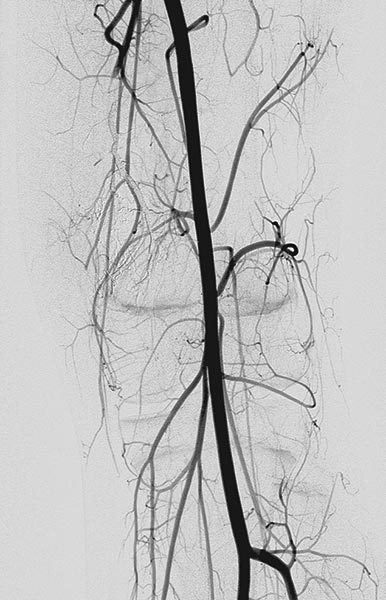

In der anschließenden Röntgen-Übersichtsangiographie sind die Fisteln vollständig verschlossen.

In gleicher Sitzung erfolgt dann noch eine Sklerosierungstherapie in Direktpunktionstechnik. Unter Ultraschallsteuerung wird die venöse Malformation anpunktiert und Kontrastmittel injiziert.

Es kontrastiert sich unmittelbar eine drainierende Vene, die in die Vena femoralis abfließt und damit mit dem tiefen Leitvenensystem kommuniziert. Diese wird mit Alkoholgel verschlossen.

Anschließend ist eine komplette Sklerosierung der VM möglich, da das Sklerosierungsmittel nicht mehr über die Kommunikationsvene abfließen kann.